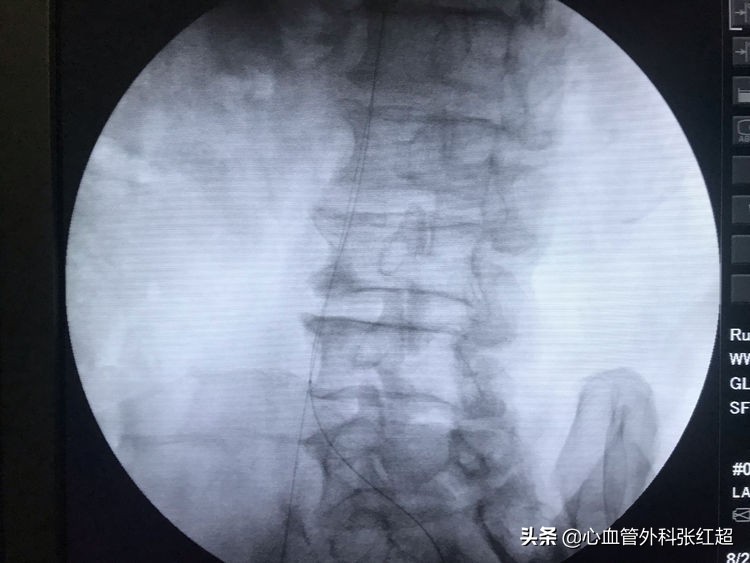

导丝进入假腔方向,加用微导管,换导丝破膜入真腔。

方位验证导丝入真腔后,用微导管造影进一步验证。